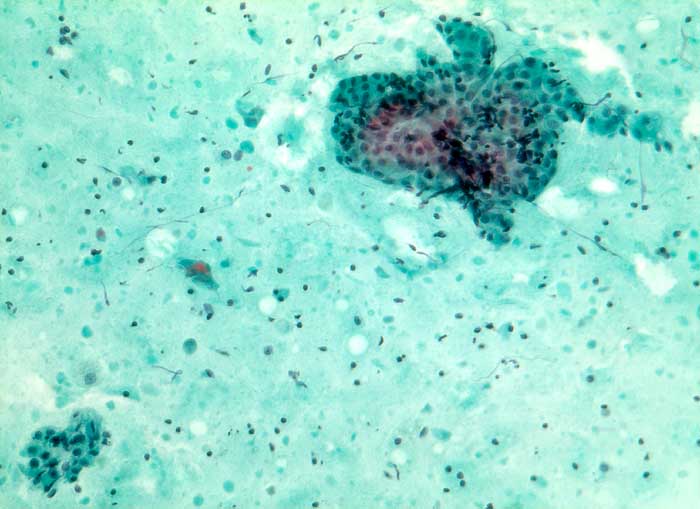

Der Warthin Tumor ist ein zystisch papillärer Tumor mit lymphoidem Stroma und einem zweischichtigen onkozytären Epithel. Schleim- oder Becherzellen und metaplastisches Plattenepithel können vorkommen. Die diagnostischen Zellen werden oftmals verdünnt durch den Zysteninhalt, was in einer falsch negativen Punktion resultieren kann. Im Idealfall enthält das Punktat Onkozyten und Lymphozyten auf granulär zystischem Hintergrund. Oftmals fehlen aber die Onkozyten. Differentialdiagnostisch muss man in solchen Fällen an eine lymphoepitheliale (oder branchiogene) Zyste denken. Onkozyten kommen bei einer Vielzahl anderer Parotisläsionen vor: onkozytäre Metaplasie oder Hyperplasie, Sjögren Syndrom, Onkozytom, Mucoepidermoidkarzinom, Adenokarzinom, adenoidzystisches Karzinom.